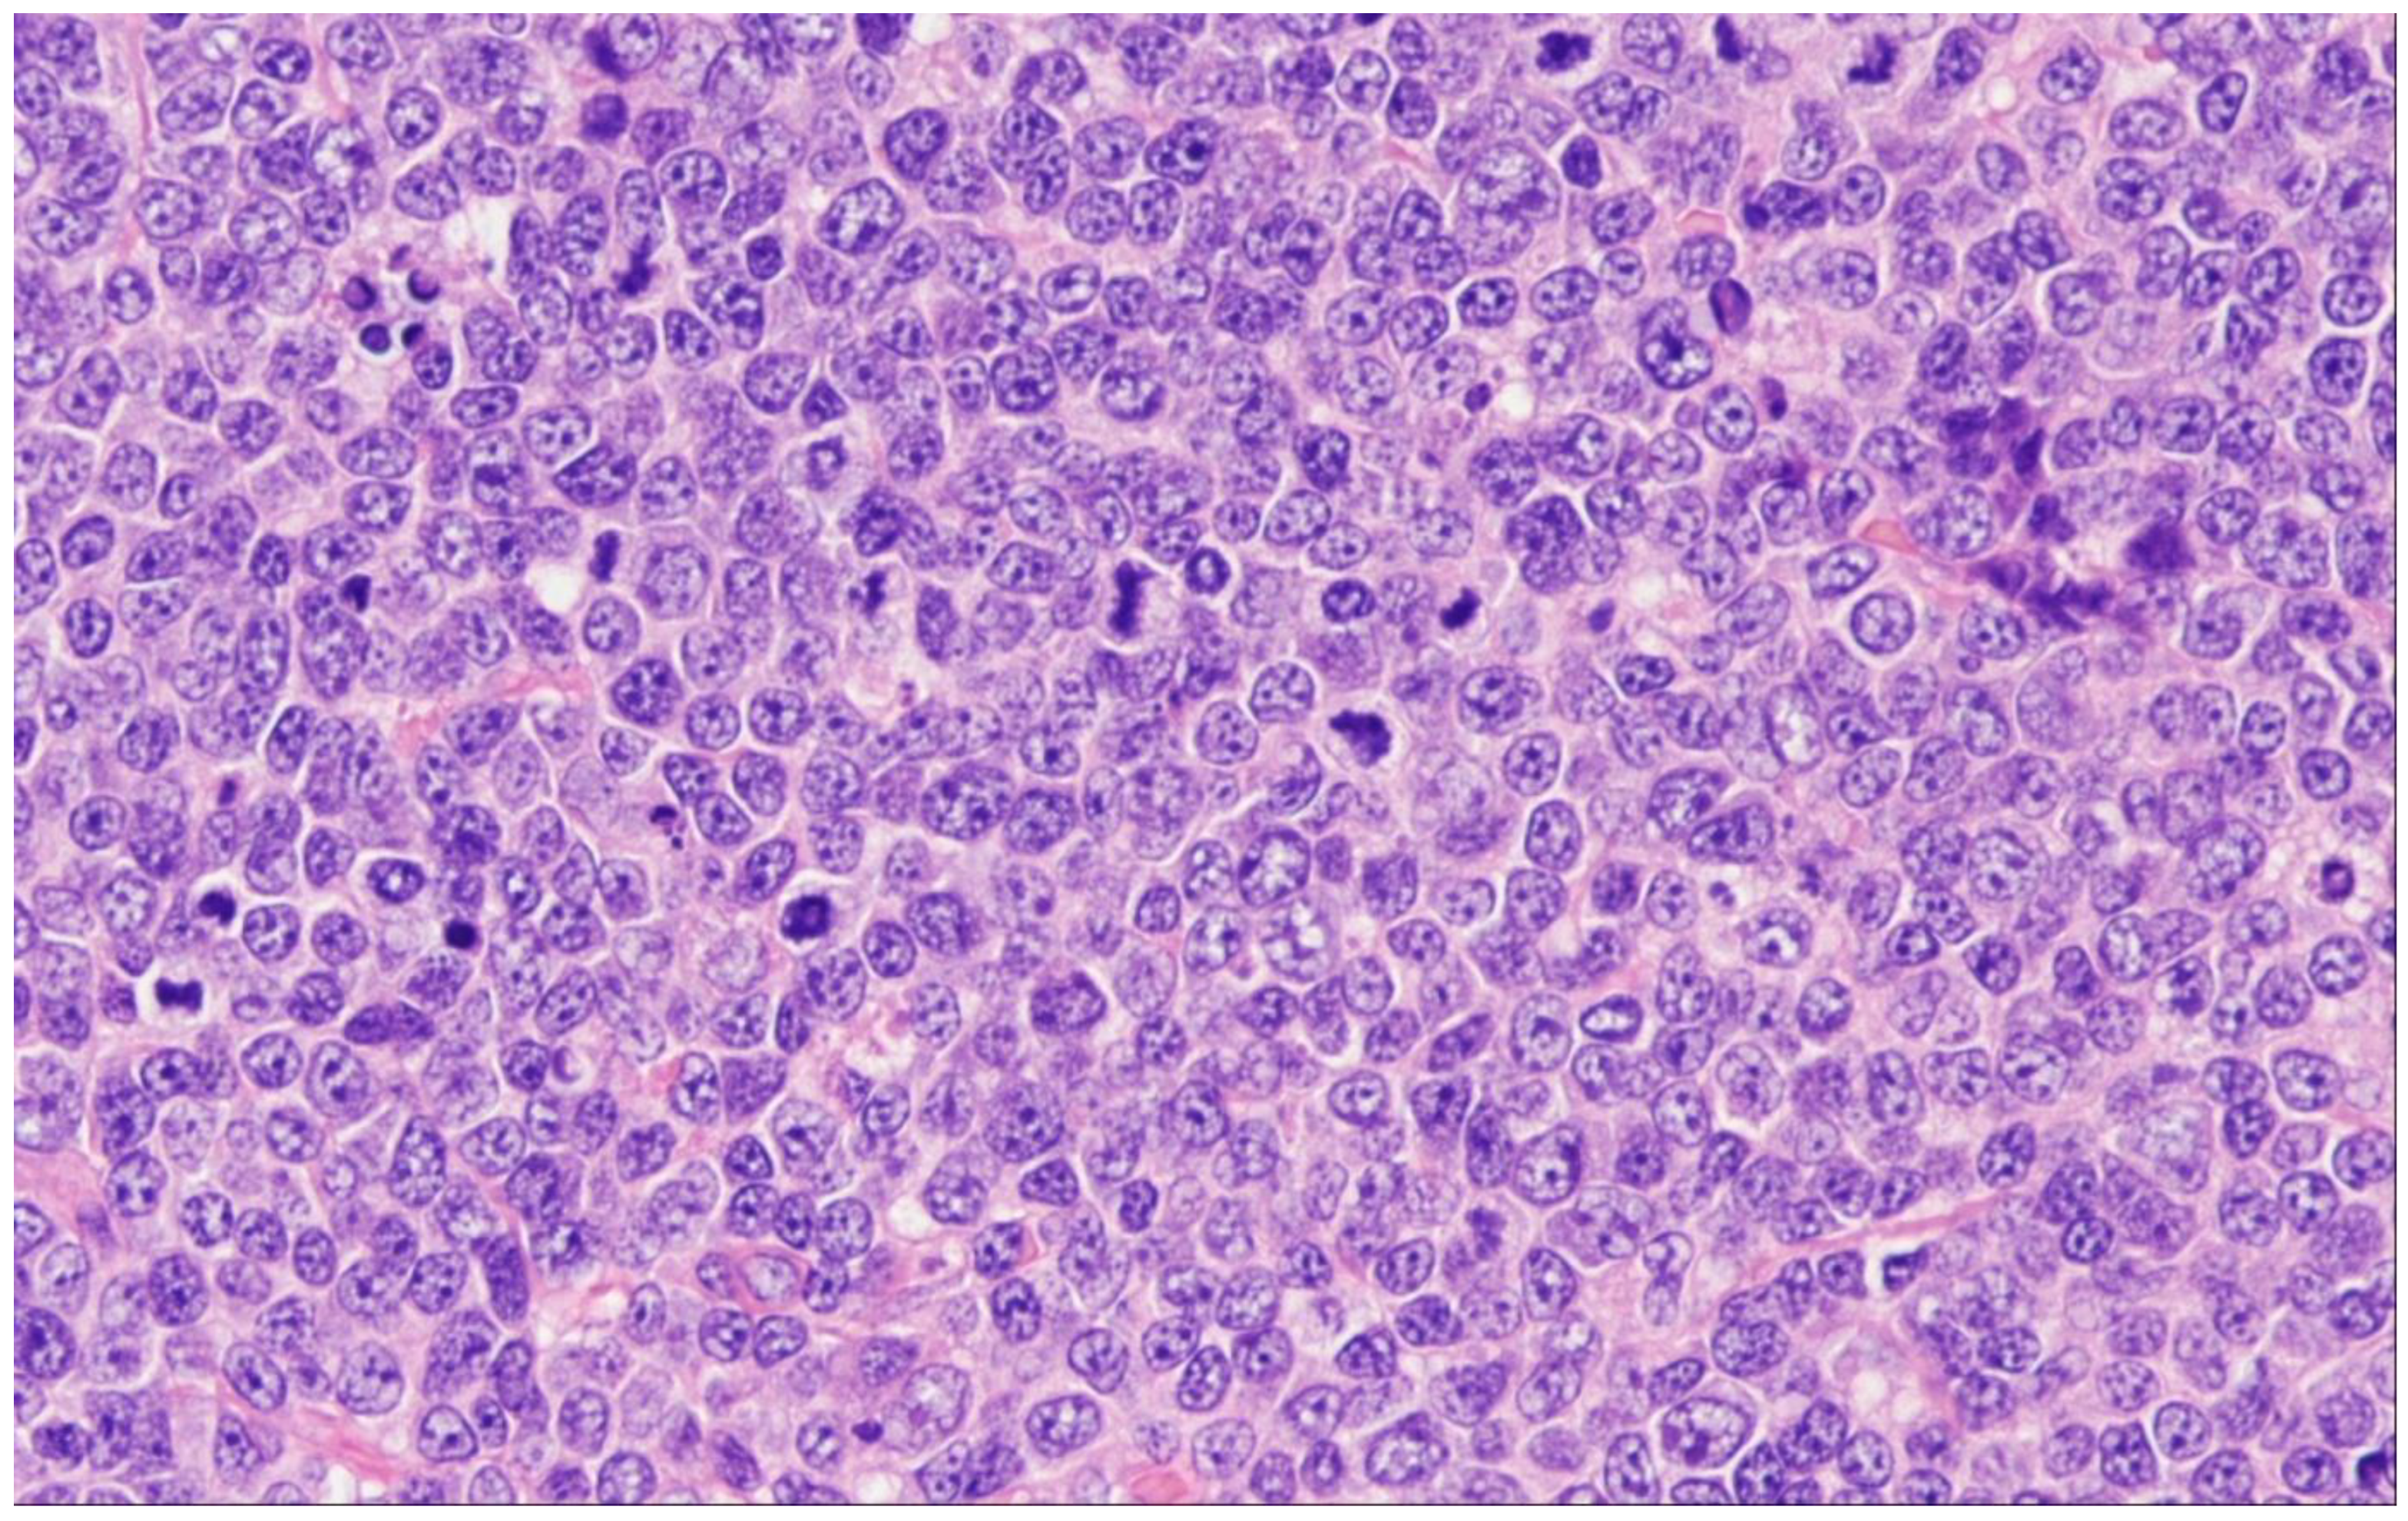

6. Predominantly Diffuse FL